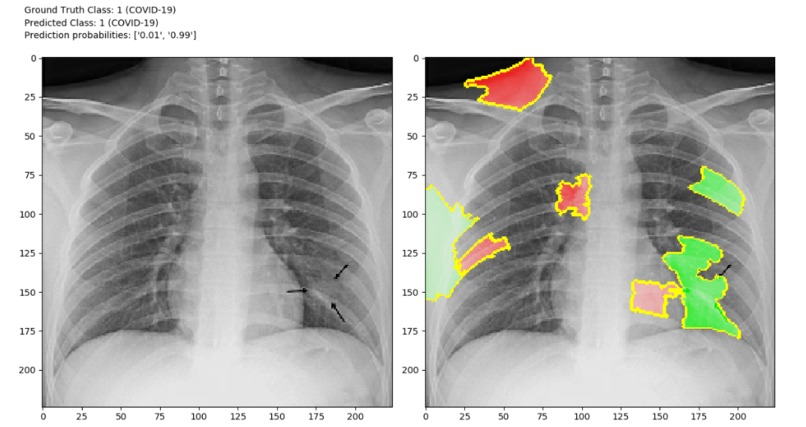

Although there is one drawback that X-ray analysis requires a radiology expert and takes significant time. Which is precious when people are sick around the world. Therefore, developing an automated analysis system is requires to save medical professionals valuable time.we can identify the difference in those two images. So, we can create a software which can identify difference between those two images using image processing techniques and Artificial Intelligence. We can Train AI model with features of normal person’s X-ray data and COVID19 patient’s X-Ray image data.

Detection of COVID19 symptoms is not only essential but also difficult task as it is current pandemic. COVID19 affects the lungs so if we detect in few seconds it will save doctors and health workers valuable time.

The primary objective is to develop the automated system that will detect the symptoms of COVID19 using X-Ray image.The secondary objective is to identify case of COVID19 positive or negative. Our goal is to use X-ray or CT images to develop AI based approaches to predict and understand the infection. We will release these models using our open source Chester AI Radiology Assistant platform which is designed to scale to a global need by performing the computation locally.